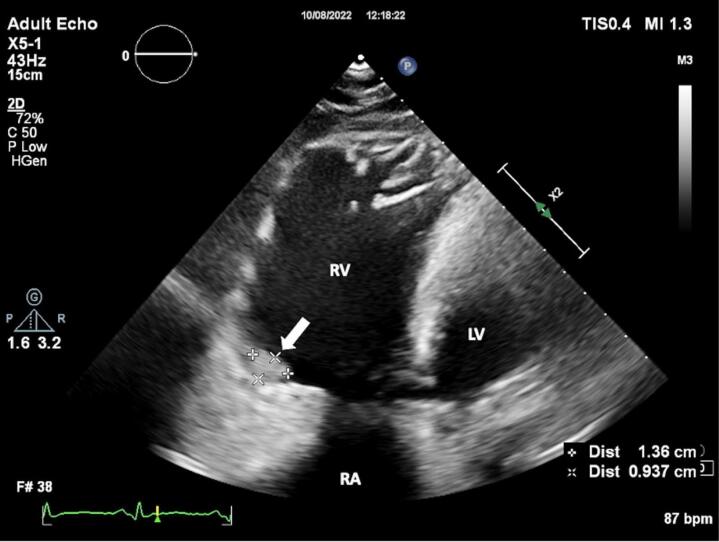

Herein we present a case of a right ventricular (RV) thrombus in a patient with arrhythmogenic cardiomyopathy (ACM). The 24-year old female patient was diagnosed with ACM after echocardiography, genetic test and cardiac magnetic resonance imaging. Interestingly, at echocardiography, an unusal thrombus formation was detected at RV lateral wall. Also, CMR confirmed the thrombus and oral anticoagulant therapy was started. During the patient's follow-ups, it was observed that the imaging consistent with the reported thrombus disappeared after effective anticoagulant treatment. After the diagnosis was confirmed with genetic tests, an implantable cardioverter-defibrillator (ICD) was implanted in the patient with a high sudden cardiac death (SCD) risk score. Even in arrhythmogenic right ventricular cardiomyopathy patients thrombi are rarely reported. However, the development of imaging techniques may enable more frequent detection and effective treatment of thrombi in these patients.